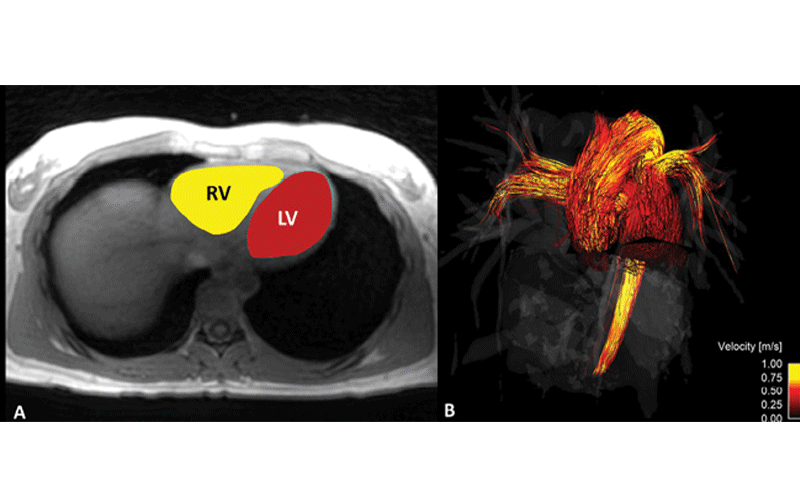

Advances in a powerful new technology, 4D flow MRI, offer a comprehensive picture of the heart and aorta. The fourth dimension, movement, allows for better visualization of blood flow through the cardiovascular system, potentially identifying areas that require follow up. A recent study published in Radiology: Cardiothoracic Imaging, “Two-Minute k-Space and Time–accelerated Aortic Four-dimensional Flow MRI: Dual-Center Study of Feasibility and Impact on Velocity and Wall Shear Stress Quantification,” demonstrated that 4D flow MRI can depict significant differences in how the heart contracts between men and women. (See image below.)

The study showed that kinetic energy during contraction was significantly higher in men, while vorticity and strain were higher in women. Because these results were found in healthy volunteers, the research team, led by Emilie Bollache, PhD, of the Department of Radiology, Northwestern University in Chicago proposed that blood flow metrics could be useful reference standards for evaluating disease.